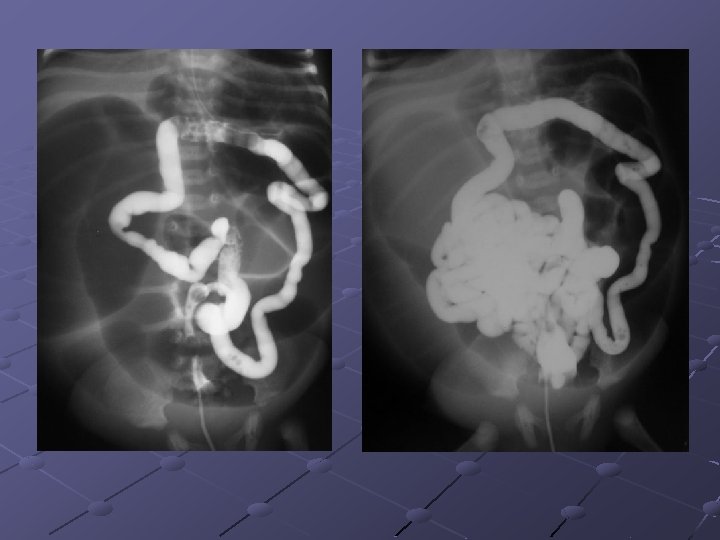

Cas n° 3 Garçon de 19 ans Pas d’antécédents particuliers Douleurs et distension abdominales, vomissements Examen distension diffuse, pas de signes de péritonite

« northern exposure sign » « coffee bean sign »

Volvulus du colon sigmoïde Cause fréquente de volvulus( segment long et mobile) ASP couché ( « coffee bean sign » ) pose le diagnostic dans 80% des cas Origine congénitale ou défaillance des moyens de fixité du colon ttt: décompression endoscopique suivie d’une résection élective